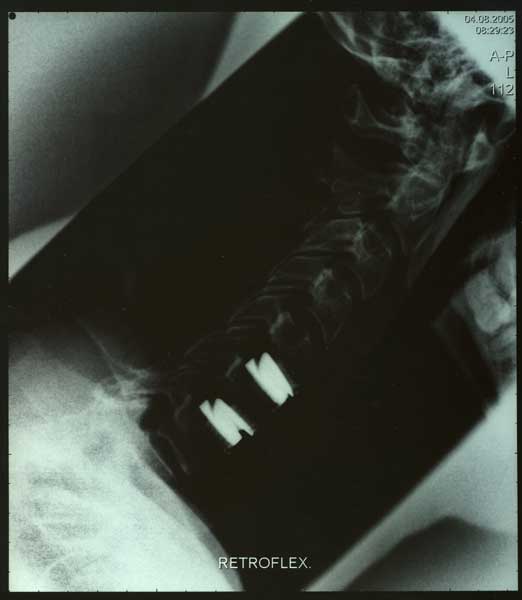

Bild 1 - 4 von links nach rechts

Bild mit Prestige-Prothese

monosegmentale Versorgung

bisegmentaler Versorgung - Retroflexion